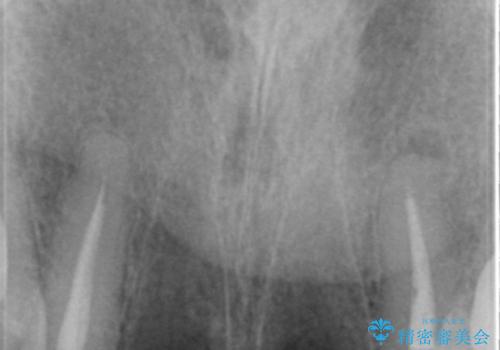

精査したところ、左上の側切歯(左上2)も破折しており保存不可能な状態でした。

左上の側切歯(左上2)を抜去し、右上の側切歯(右上2)の再根管治療後、セラミックのブリッジによる補綴を行いました。